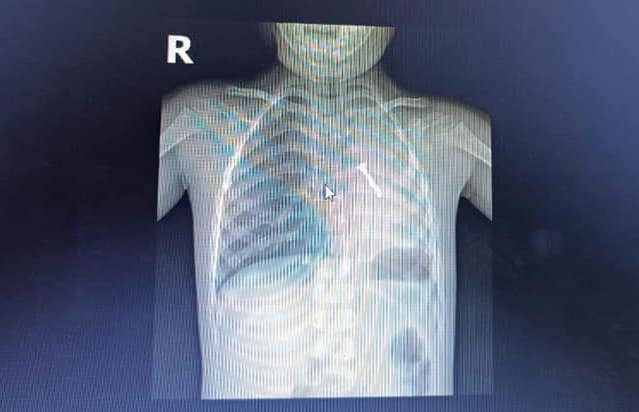

| Hình ảnh chụp X-Quang cho thấy, một chiếc đinh vít bị kẹt trong phổi trái của cháu bé. |

Tại Bệnh viện Sản nhi Nghệ An, các bác sĩ đã tiến hành thăm khám, chụp X-quang. Kết quả cho thấy có 1 chiếc đinh vít dài khoảng 3cm nằm trong phổi trái bệnh nhi dẫn đến mất hoàn toàn thông khí phổi trái.